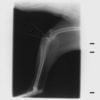

本症例は、走った後に左後肢を挙上していることを主訴に来院されました。触診時に左膝関節のクリック音を聴取、レントゲン検査にて左脛骨の前方変位が認められました。術中に、前十字靱帯の断裂及び内側半月板の損傷、内側の軟部組織の顕著な腫脹を確認。半月板切除、TPLOを実施しました。周囲組織への炎症の波及もあったため回復に時間を要しておりますが、徐々に跛行頻度は減少傾向にあり、現在も経過観察中です。術前に約29°あったTPAは術後に約10°まで矯正されました。

術前写真

手術前後のTPA(脛骨高平部の角度)を測定しています。

約29°から約10°へ矯正されています。